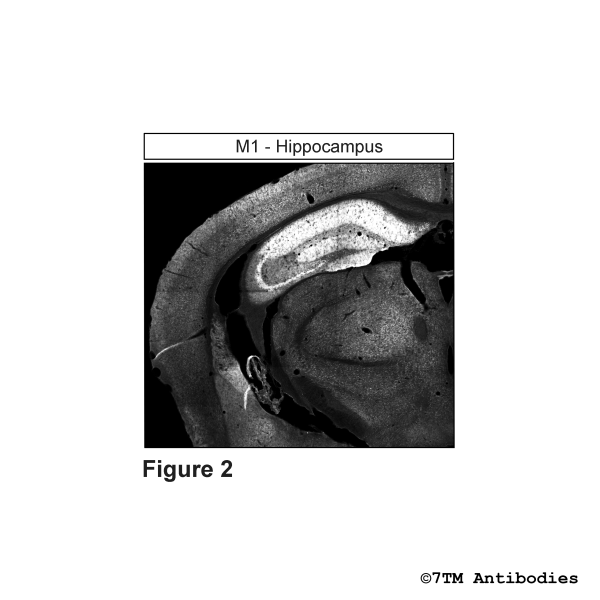

The non-phospho-M1 receptor antibody is directed against the 3rd loop of human M1 Muscarinic Acetylcholine Receptor (M1). It can be used to detect total M1 receptors in Western blots independent of phosphorylation. The non-phospho-M1 antibody can also be used to isolate and enrich M1 receptors from cell and tissue lysates. It also detects M1 in cultured cells and tissue sections by immunohistochemistry.